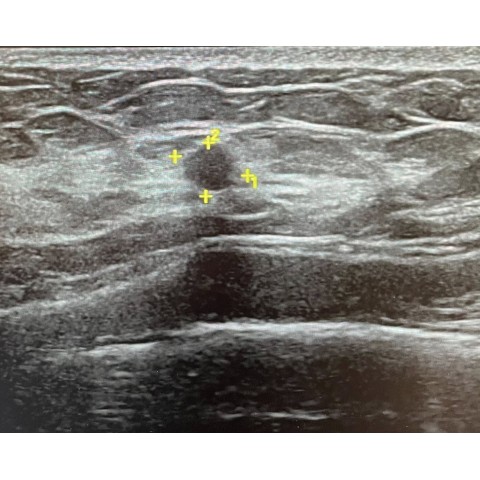

乳房硬塊切片檢查

【陳尹陽醫師|乳房外科臨床案例】乳房超音波追蹤:為什麼看起來小小一顆,也可能要切片? 案例分享:0.3 公分的小腫瘤,半年後為什麼立即建議切片? 這位患者半年前在外院做乳房超音波,發現一顆 0.3 公分的小腫...